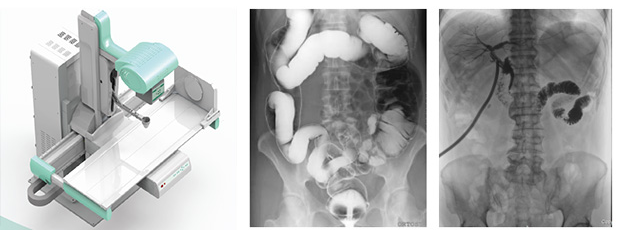

多功能動態(tài)dr由動態(tài)平板探測器、高壓發(fā)生器、球管、運動機架、計算機與圖像處理與傳輸系統(tǒng)組成,與傳統(tǒng)數(shù)字化X線攝影技術相比,動態(tài)多功能dr攝影能在一個時間單位內(nèi)低劑量高速獲得多幀X線影像,通過圖像算法處理系統(tǒng)后,極速輸出一段連續(xù)動態(tài)影像(運動),實現(xiàn)所見即所得。

多功能動態(tài)dr是集合拍片,透視,造影三種功能為一體的設備。可以對特殊病灶部位進行高速實時點片,捕獲高清病灶圖,降低了漏診誤診率。特別是對不能配合的患者,也能進行快速高效的檢查,大大減輕了患者的痛苦。